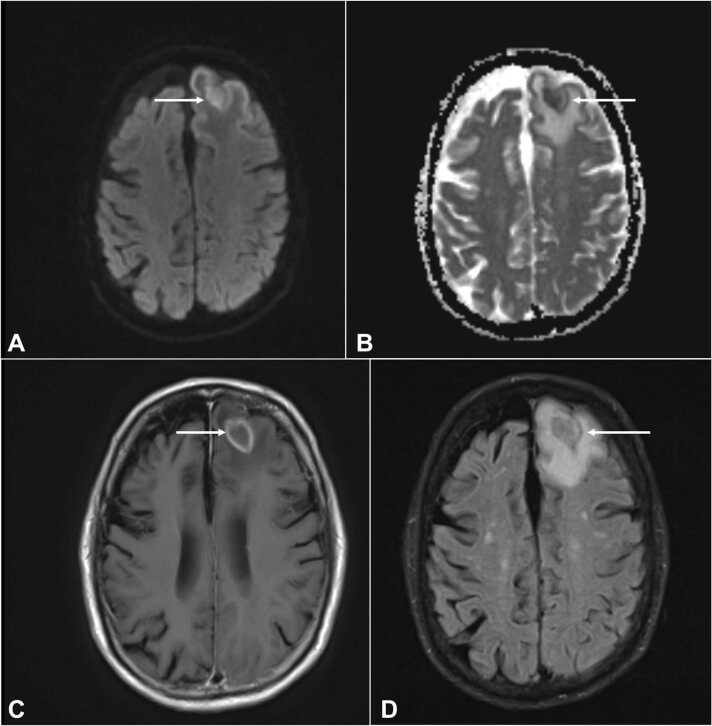

Laboratory workup was significant for a leukopenia of 3990 per μL. Respiratory viral panel was negative, chest x-ray did not show any acute cardiopulmonary process, and urinalysis was unremarkable for infection. Blood and urine cultures for bacteria and fungus were negative. HIV antigen/antibody test was non-reactive. Given abnormal CT head findings, a magnetic resonance imaging (MRI) of the brain was done and revealed peripherally enhancing lesions in the left frontal and occipital lobes (Fig. 1, Fig. 2), which was thought to be consistent with metastases. The patient was initiated on intravenous dexamethasone and referred to an oncologist for further treatment of presumed metastatic lymphoma to the brain. His mycophenolate mofetil (MMF) for his myasthenia gravis was slowly tapered given his disease was quiescent for years.

Fig. 1.

Rim enhancing lesion in the left frontal lobe with extensive surrounding vasogenic edema, associated with restricted diffusion within the brain shown with arrows in DWI [A], axial ADC [B], axial T1 [C], and FLAIR [D] sequences of MRI brain without contrast. DWI = diffusion weighted imaging; ADC = apparent diffusion coefficient; MRI = magnetic resonance imaging.